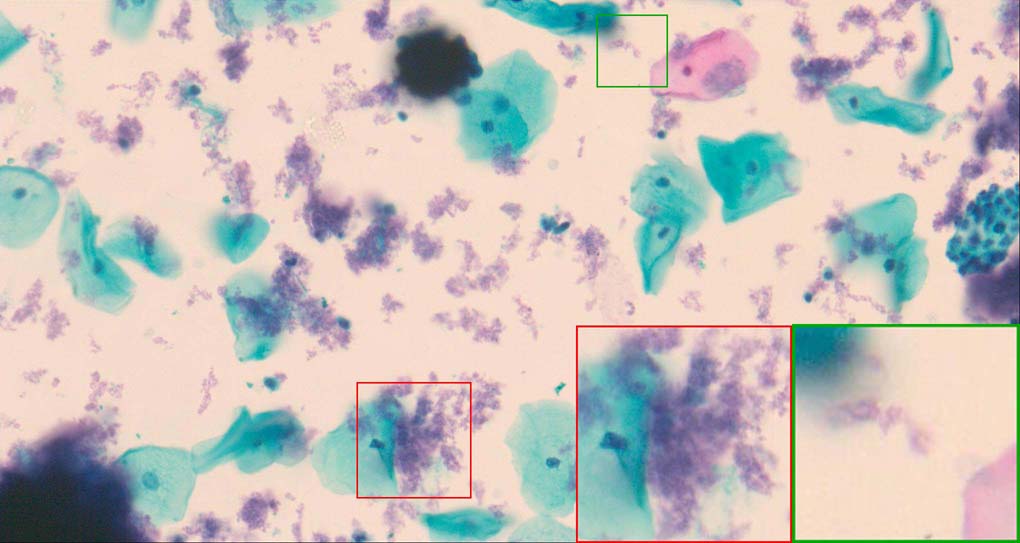

A good image fusion method should contain the following properties. First, it preserves both the details of small size objects and the integrity information of large size objects in the fused image, even in the case of the size of the interested objects varying largely in the image. For example, the cervical cell images from the microscope contain both small size isolated cells and large size agglomerates, which are both useful for cervical cytology [5]. Second, it should be efficient enough to handle large-scale data. For instance, it needs to process thousands of fields of view (FoV) in an acceptable time for the whole slide scanning in digital cytopathology [6], which requires to fuse a series of high resolution images captured at each FoV in a very efficient way. Third, it does not produce obvious artifacts. Despite being studied extensively, to our best knowledge, existing fusion methods may not meet these requirements simultaneously.

To demonstrate the effectiveness and efficiency of the proposed image fusion method , we conduct a set of comparative experiments on three image datasets. The first is composed by 8 pairs of multi-modal medical images and the second one contains 15 pairs of multi-focus gray or color natural images. These two datasets are often used in many related papers and some examples are shown in Figure 3(a) and Figure 3(b). The third one is a new multi-focus cervical cell image dataset collected by ourselves, which consists of 15 groups of color images and each group contains a series of multi-focus cervix cell images with size of or , etc. Some source examples are shown in Figure 3(c). Our source code implemented in C++ along with the new multi-focus cervical cell image dataset is available online.

Figure 9, Figure 10 and Figure 11 show the comparative fused results of the multi-focus cell images shown in Figure 3(c). For clarity, we also present a closeup view in the right-bottom of each sub-picture in Figure 9 and Figure 10. As shown in the close-up views of Figure 9, the fused images based on DSIFT, IM, MWGF and BF methods are extremely blurred in the boundary and fail to keep the details of cell nucleus. Furthermore, the DTCWT and NSCT based methods produce halo artifacts in the fused images, while GFF and CNN based methods fail to preserve the small cell nucleus. LP-SR based method nearly works fine which keeps the most of the details of the small size cells, but the integrity of the clustered large size cells is damaged. Fortunately, in our proposed method, the integrity of the clustered large size cells is preserved and most of the isolated small size cells are maintained from the original images, which demonstrates the best visual quality.

Similarly, as shown in the close-up views of Figure 10, the fused images from DSIFT, IM, MWGF and BF are blurred and lose some nucleus details, while the results from DTCWT, GFF, CNN and NSCT produce halo artifacts. LP-SR based method can keep details well but also produces halo artifacts and other noise. Our method can preserve the focused areas of different source images well without introducing any artifacts. For the example illustrated in Figure 11, the fused images generated by DSIFT, DTCWT, IM and NSCT all fail to preserve the focused areas of different source images and result in extremely blurred images. The GFF, CNN, MWGF and BF based method introduces a lot of color distortion of the nucleus regions and the obvious halo artifact. The result of LP-SR based method is close to the one of our method but introduces some odd color distortion. Again, our method produces fused image which can preserve the focused areas of different source images well without introducing any artifacts.